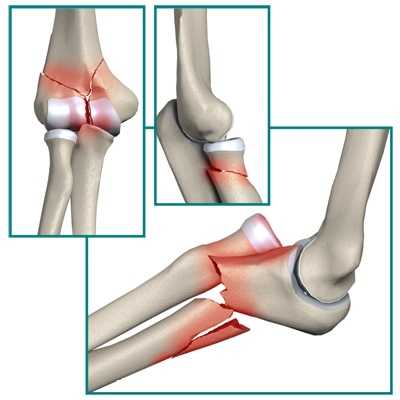

Показаниями к артроскопическому лечению могут быть: переломы головки лучевой кости, венечного отростка, головочки плечевой кости (головчатого возвышения).

Основная функция головки лучевой кости — это стабилизация локтевого сустава. При переломах головки или ее удалении появляются нестабильность и боль в локтевом суставе.

Венечный отросток играет большую роль в стабильности локтевого сустава. Травмы венечного отростка обычно сочетаются с повреждением связок.

При значительных переломах венечного отростка требуется операция поегорефиксации. Если операция по каким-либо причинам не выполнялась, возможно развитие нестабильности локтевого сустава, которая в будущем приведет к тяжелому артрозу. Репозиция и фиксация венечного отростка, а также восстановление связочного аппарата приводит к снижению риска подобных осложнений. Венечный отросток находится очень глубоко внутри сустава, возле него проходит множество важных нейро-сосудистых образований, в связи с чем открытая операция по его рефиксации требует большого разреза кожи и может быть чревата осложнениями. По этой причине операции под контролем артроскопа, будучи менее травматичными, имеют безусловное преимущество.